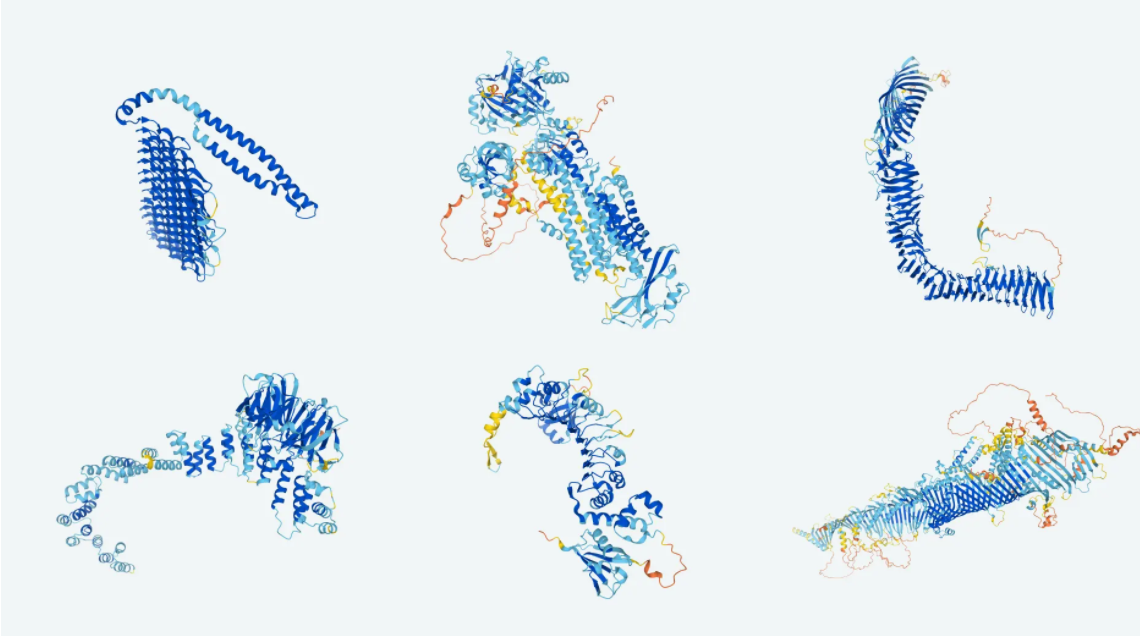

🧬 DeepMind släpper databas över alla kända proteinformer i världen

DeepMind har skapat en AI som kan förutsäga formen av ett protein med exaktheten av bråkdelen av en atomsbredd. Nu ger företaget tillgång till formen av miljoner proteiner i en öppen databas.